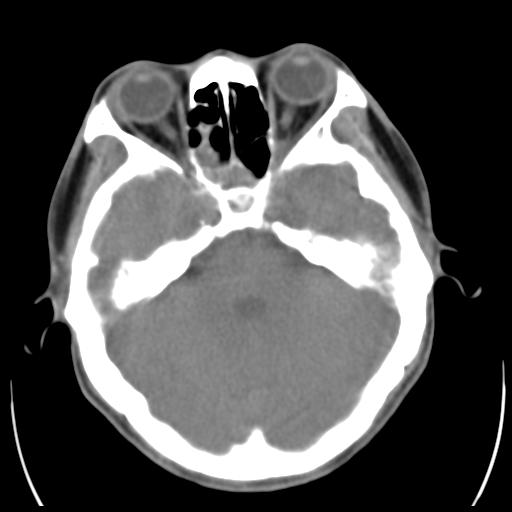

35m 鼻子时不时流血,头及右侧面部痛,颈部淋巴结未见明显大

这个东西大家仔细看看呀

考虑鼻咽癌侵犯颅底并突入右侧鼻腔;双侧中耳乳突炎。

蝶窦,后组筛窦及鼻咽部团块状软组织影,骨壁破坏,病变较广泛。考虑恶性肉芽肿。建议活检。

颅底骨质明显破坏 支持鼻咽癌 但病灶的边缘毛糙 不能除外炎性

考虑中线肉芽肿(鼻硬结病),次之tb或真菌感染性肉芽肿,病变形态不像肿瘤,建议增强及活检。

建议:必要时行鼻咽镜检查(活检)进一步明确诊断。